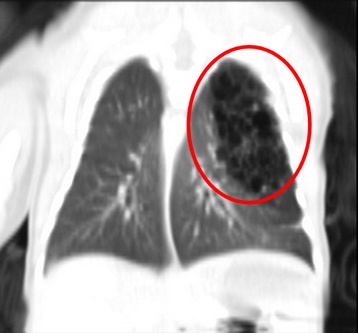

右圖:電腦斷層影像顯示,小敬的左上肺葉被類似囊泡樣的組織取代。

「先天性肺部呼吸道畸形」是指肺葉被類似囊泡樣的組織取代,而沒有正常的肺泡,無法進行氣體交換,甚至壓迫到縱膈腔造成心臟血管偏移,發生率大約是每25000~35000名新生兒中會出現一名,十分罕見。兒童外科楊筱惠醫師表示,小敬媽媽做產檢時並未發現異常,且生產過程順利並無早產,但小兒主治醫師張宇勳主任和照護小敬的醫護團隊十分警覺,發現孩子出生後出現呼吸喘的情形,很快地被轉往新生兒加護病房(PICU)並做X光檢查,從影像中發現小敬的左上肺葉有一些「囊泡」模樣的東西,判斷這可能是「先天性肺部呼吸道畸形」,於是後續再幫他做電腦斷層,確定符合診斷。